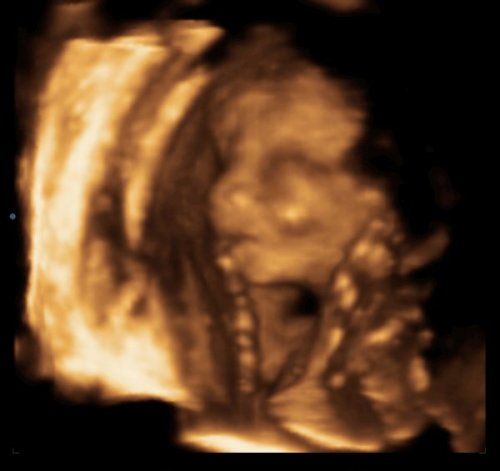

arc: Kép